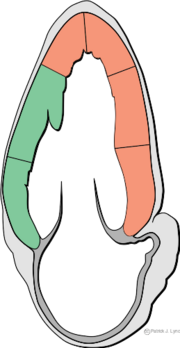

| 22:22, 16 June 2008 | Heart apical 2c myocardial regions.svg (file) |  |

15 KB | Vdbilt | 1 | |